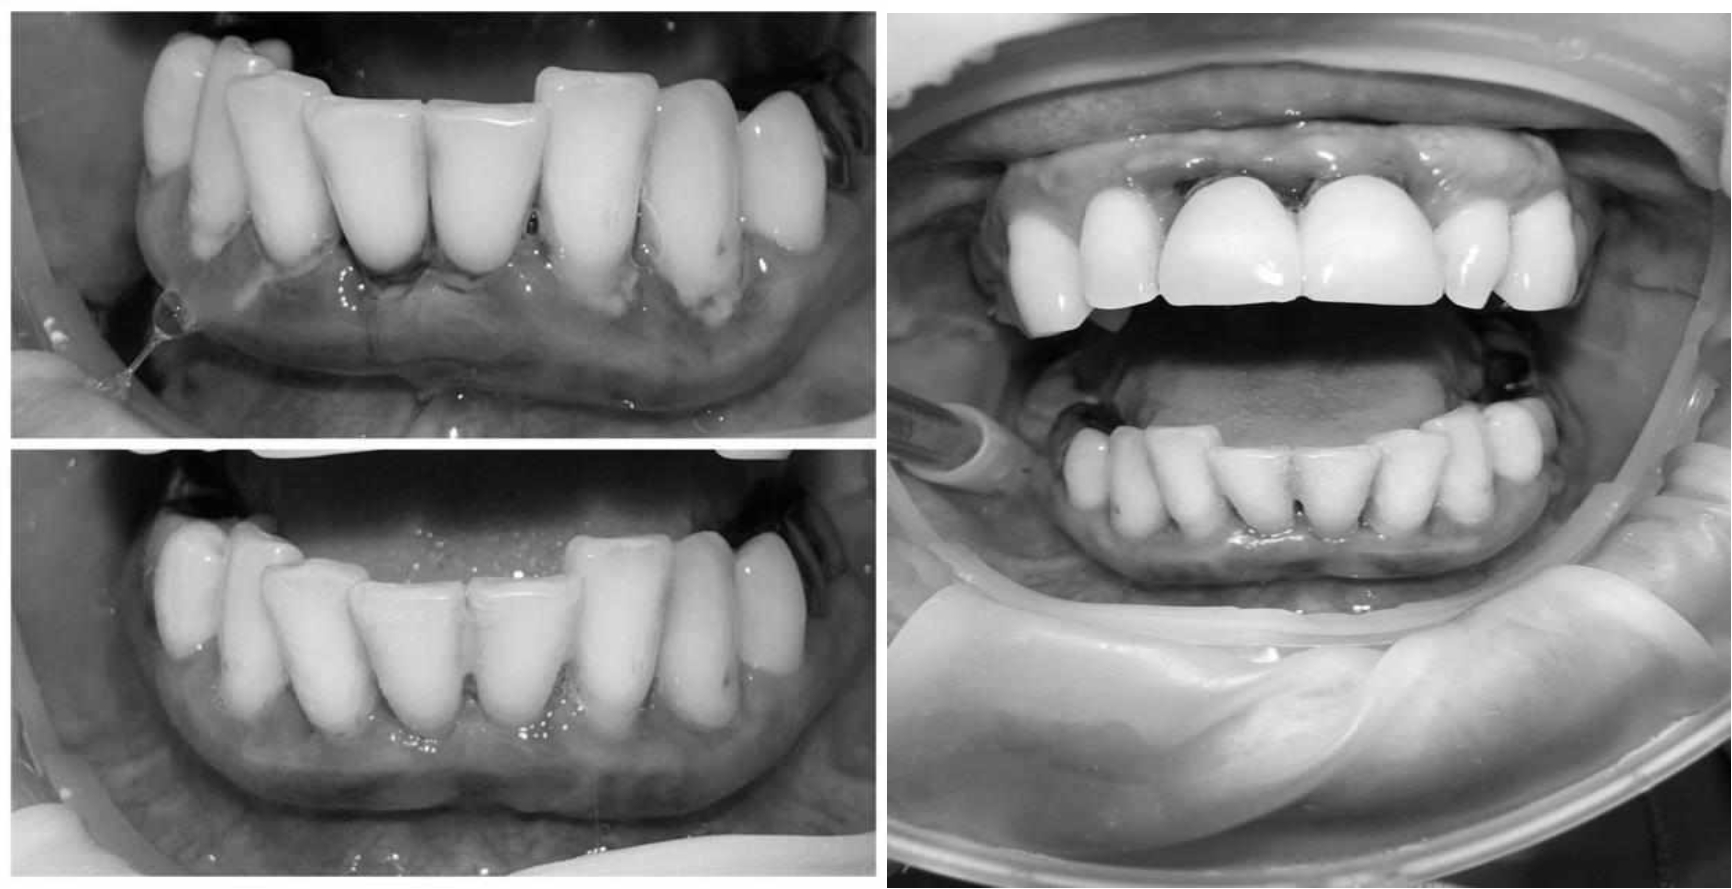

За пародонтологическим лечением обратилась женщина 61 года с жалобами на неприятный запах из полости рта, кровоточивость десен при чистке зубов, подвижность зубов, несостоятельность ортопедических конструкций.

Ранее у пародонтолога не наблюдалась. При осмотре выявлены: неудовлетворительная индивидуальная гигиена полости рта, пародонтальные карманы до 7 мм, обильная кровоточивость и гноетечение из пародонтальных карманов, подвижность зубов 4.2, 4.1, 3.1, 3.2 II степени, обильные над- и поддесневые зубные отложения (рис. 1). На ортопантомограме отмечается резорбция костной ткани до ½ длины корня, очаги остеопороза (рис. 2). Пациенту был поставлен диагноз хронический генерализованный пародонтит тяжелой степени тяжести. При осмотре была составлена пародонтограмма с использованием компьютерного зондирования (рис. 3).

Рис. 2. Ортопантомограмма исходной ситуации пациента состояния полости рта